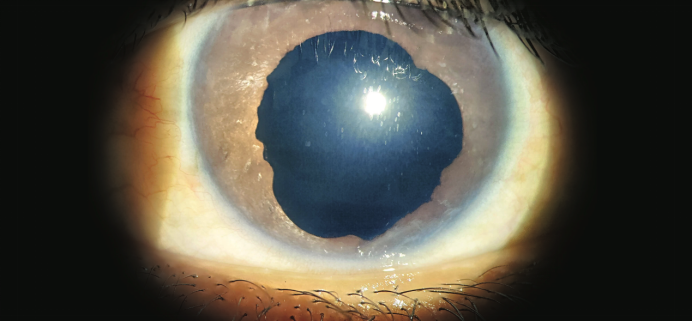

裂隙灯检查发现患者左眼虹膜受损,瞳孔欠圆、扩张固定,晶体缺如。(见图1)

图1. 左眼虹膜受损,瞳孔欠圆、扩张固定,晶体缺如